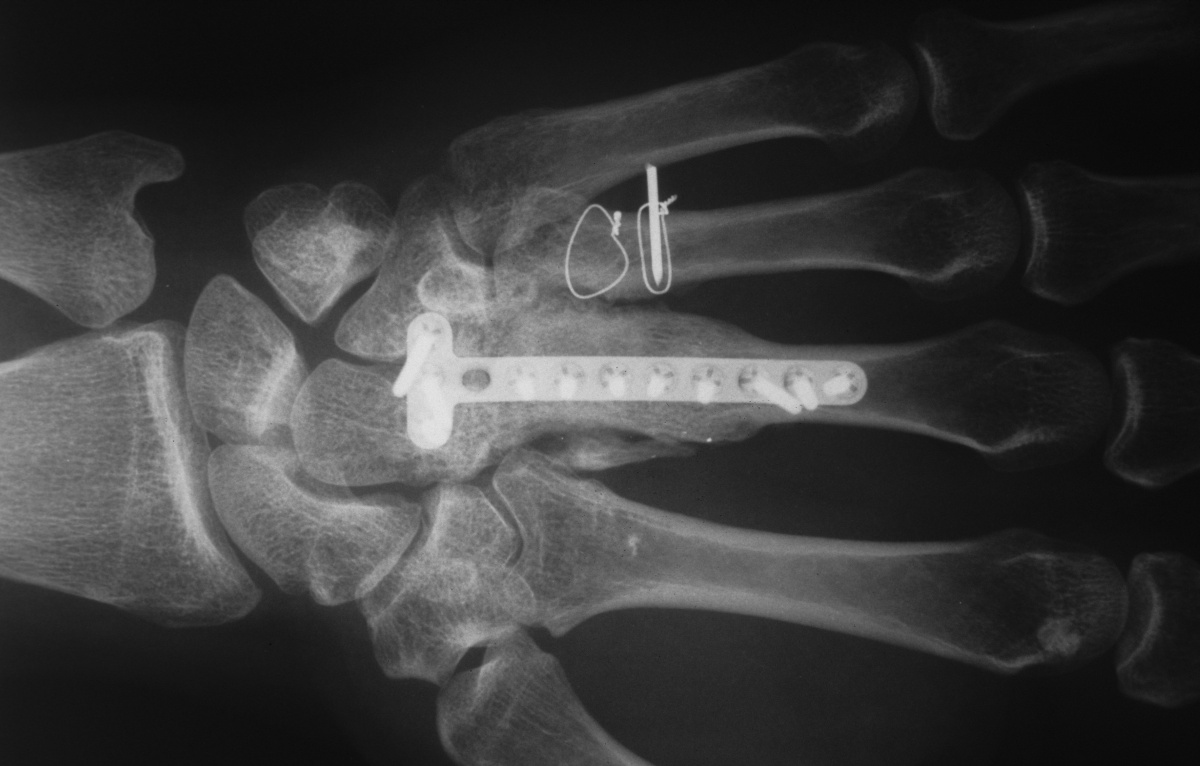

| Three months

postop; bone graft incorporated, active motion

restored, recovery of sensation. |